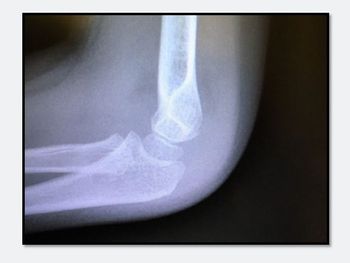

What type of injury is seen on this x-ray of a young boy's elbow? Outward signs of trauma are negligible.